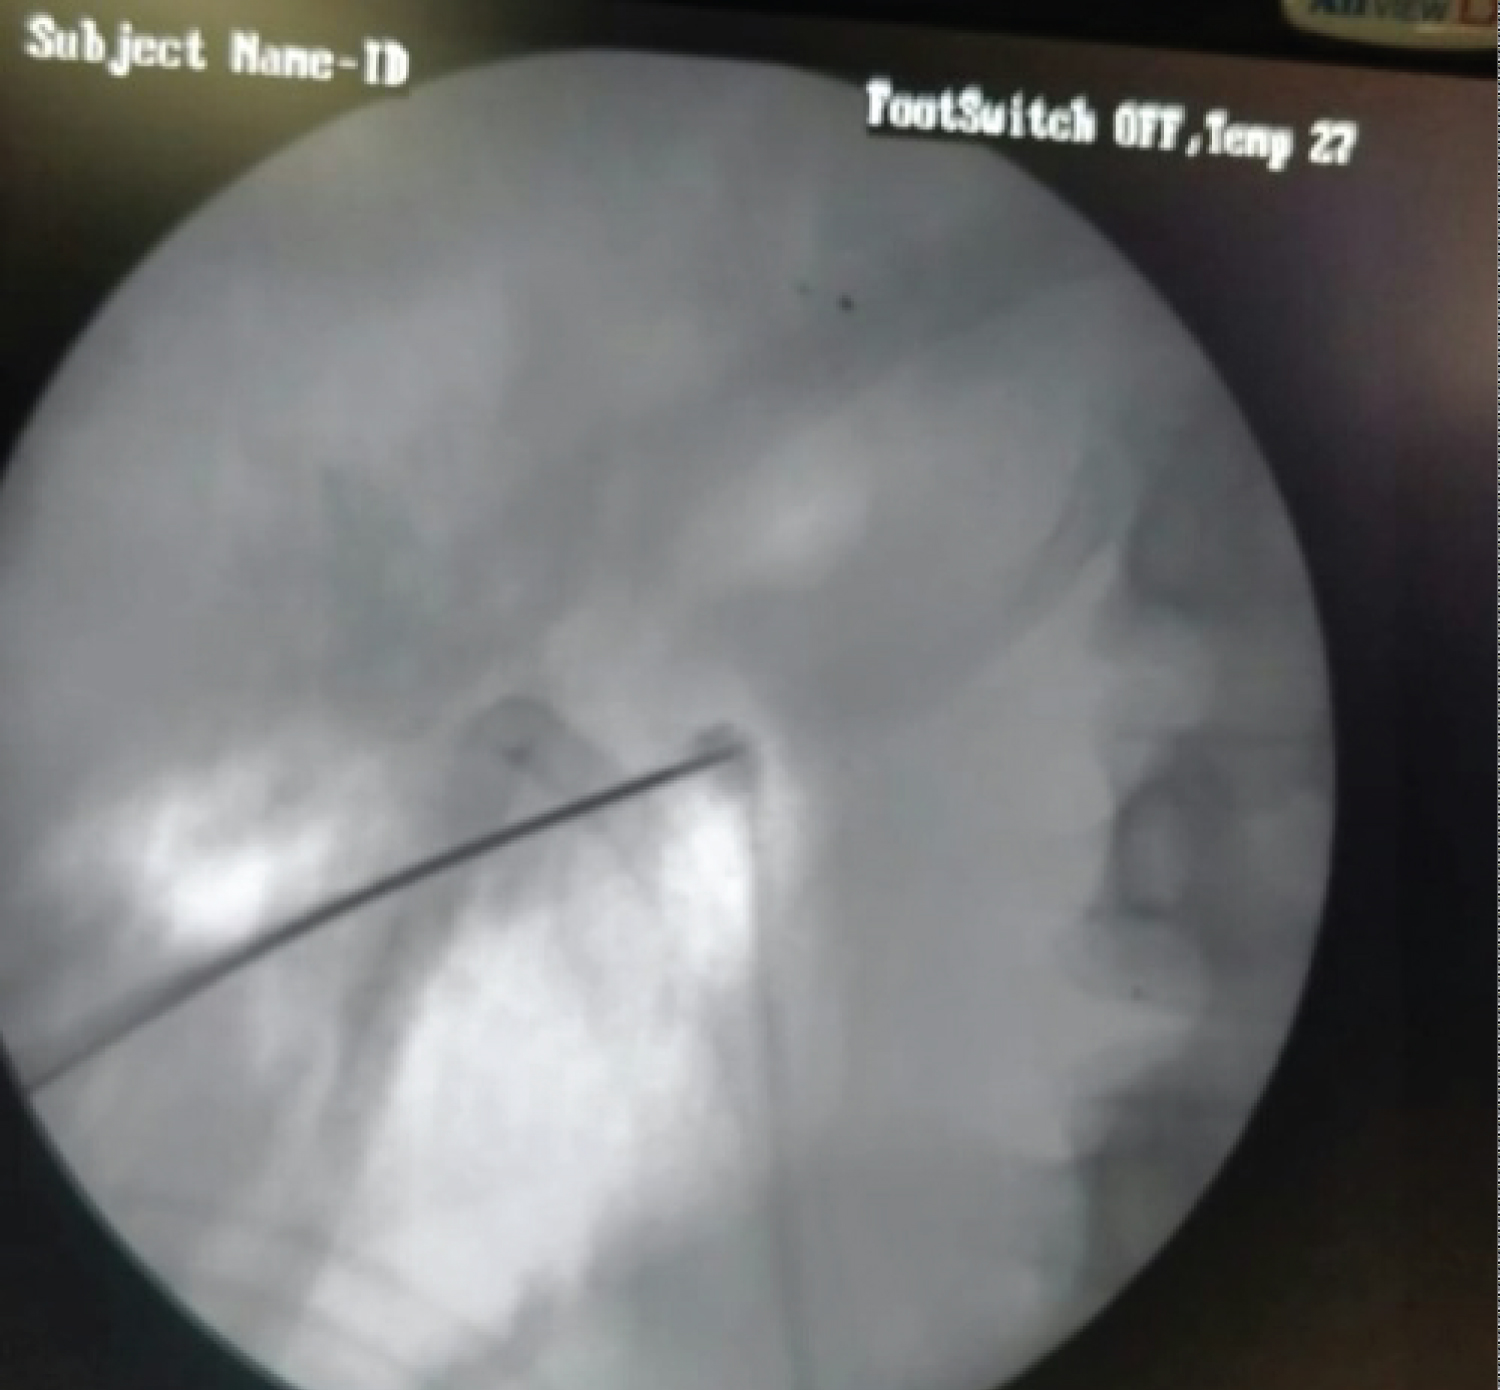

A 32-year-old male underwent PCNL for renal pelvic calculus extending into the middle calyx. A middle calyceal puncture was made but glide wire could not be safely parked into the Pelvicalyceal system (PCS). After repeated attempts to pass the guide wire into the collecting system, guide wire was removed with puncture needle in place. During removal the jacket of the glide wire got stripped and lost into the renal parenchyma. Another calyceal puncture was made and tract dilated and stone was removed. There was no endoscopic trace of the stripped glide wire in the PCS, though it was visible in fluoroscopy. Every calyx was searched but the stripped wire could not be seen. A DJ stent and nephrostomy tube was placed and procedure abandoned. Postoperative X-ray was showing the stripped glide wire coiled in the renal area (Figure 1). After two days patient was again taken to Operation Theater after proper planning to remove the residual glide wire. Under fluoroscopic guidance the puncture was made directly on the stripped wire (Figure 2). A new glide wire was into the PCS under fluoroscopic guidance. Tract was dilated to 12 Fr and 8.5 Fr ureteroscope was passed through the sheath. The stripped wire was identified (Figure 3) and removed intact (Figure 4). Postoperative period was uneventful.

Figure 2: Fluoroscopic puncture made directly on the glide wire fragment. View Figure 2